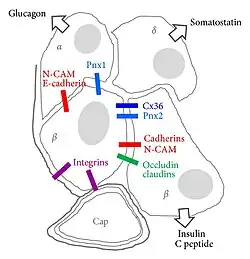

Celmembraanspecialisaties tussen endocriene cellen zijn gap junctions of zonula occludens.[13][14]

Bètacellen bereiken een nauwkeurige controle van de insulinesecretie door middel van uitgebreide cel-celcommunicatie met de andere celtypen in het eilandje van Langerhans, met name de glucagonproducerende alfacellen en de somatostatineproducerende deltacellen.[26] In bètacellen is de stijging van de bloedglucosespiegel (glycemie) na voedselinname direct gekoppeld aan insulineafgifte. Insulineafgifte is glucoseafhankelijk en wordt, naar analogie van de excitatie-contractiekoppeling in spieren, het stimulus-secretiekoppelingsmechanisme genoemd.